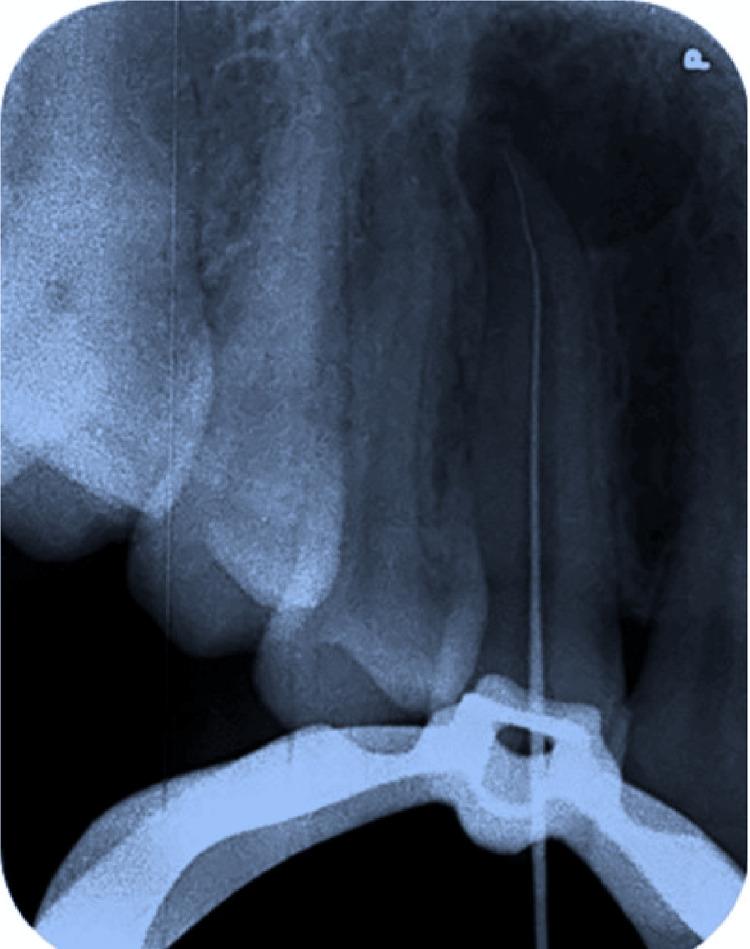

牙髓感染主要涉及革兰氏阴性厌氧菌菌群,由于这种感染,根尖周区域会发生免疫反应,这被称为根尖周病变。这种病变在X射线上可能表现为透射(暗)区,表明根尖周炎症和感染。其患病率取决于年龄、口腔卫生维护和牙科护理等因素。男性比女性更容易受到这种感染的影响。根尖周病变有两种治疗方式:手术或非手术牙髓治疗。改良三联抗生素糊剂(TAP)由环丙沙星、甲硝唑和克林霉素按1:1:1的比例配制而成,最初是专门为治疗牙髓坏死的牙齿而制备的,并支持牙齿复活和再生方案。该治疗在消除根管系统中的细菌方面非常成功。它对多种通常与牙髓感染相关的细菌具有广谱抗菌活性。改良TAP通常在根管内放置预定时间,然后取出,接着进行根管冲洗,这有助于从根管中清除微生物。非手术治疗应始终优先于手术方法,以避免更具侵入性的操作。

Infection of the dental pulp involves mainly Gram-negative, anaerobic bacterial flora and due to this infection, the periapical area experiences an immunological response, which is termed a periapical lesion. This lesion may appear as a radiolucent (dark) area on X-rays, which indicates periapical inflammation and infection. Its prevalence depends on factors such as age, oral health maintenance, and dental care. Men are more likely to be affected by this infection than women. There are two modalities for the treatment of periapical lesions: surgical or non-surgical endodontic therapy. The modified triple antibiotic paste (TAP) comprising ciprofloxacin, metronidazole, and clindamycin in the ratio of 1:1:1 was first prepared expressly to treat the teeth with necrotic pulp and to support the protocol for revitalization and regrowth. The treatment was very successful in eliminating germs from the root canal system. It provides broad-spectrum antimicrobial activity against a wide range of bacteria commonly associated with endodontic infections. The modified TAP is usually inserted into the canal for a predetermined amount of time and then removed followed by the irrigation of root canal, which helps to eliminate the microorganisms from the root canal. The non-surgical treatment should always be the first choice over the surgical approach so as to avoid a more invasive procedure.